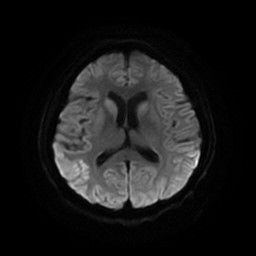

查体:生命体征平稳,神志清楚,反应迟钝,高级意识活动差,检查欠合作,眼球活动可,目光呆滞,有水平向左快向眼震,双侧瞳孔等大等圆,光反射可,双侧鼻唇沟对称,伸舌居中,喜坐位,头颈多偏斜,肩关节旋前,手指呈鸡爪样或屈曲握拳反转,双下肢屈曲,四肢肌力5级,肌张力高,腱反射正常,病理征未引出。共济检查不能配合。 辅助检查:3月25日我院颅脑DWI示双侧豆状核、尾状核稍高信号,双侧颞顶枕叶对称性片状脑回样高信号。3月30日脑电图示:1、重度异常脑电图;2、背景节律无枕区优势,全导为广泛慢波活动,睁眼节律抑制不全;3、发作期间未见明显异常波发放,5月12日脑电图示:1、重度异常脑电图;2、背景节律无枕区优势,全导为周期性双相波或三相波与弥漫性慢波活动交替出现,呈片断性连续发放,后头部为甚;脑脊液常规、生化、培养未见异常,14-3-3蛋白阴性。

诊断:亚急性海绵状脑病(CJD) 治疗并讨论:入院后患者病情进行性加重,精神障碍加重,躁动不安,出现肌阵挛,随后出现无动性缄默,间断全身大发作。予以营养神经(神经节苷脂)、抗癫痫(开蒲兰、地西泮)、抗精神症状(再普乐)等。患者转当地医院治疗。患者早期颅脑MRI未见明显异常,而随病情进一步加重出现特征性影像学及脑电图。